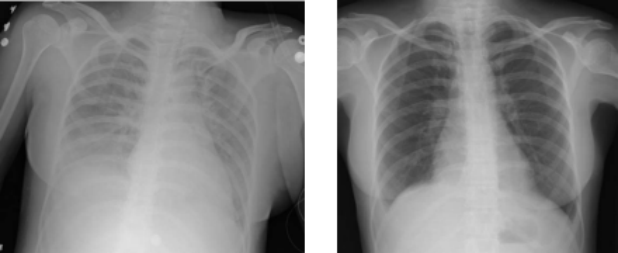

急性肺损伤(ALI)和急性呼吸窘迫综合征(ARDS)是以进行性呼吸困难和低氧血症为特征的严重疾病。它们是由肺损伤引起的过度全身性炎症反应引起的。目前的治疗主要集中在支持性治疗上,但仍然缺乏有效的靶向治疗。

间充质干细胞在治疗ALI/ARDS的临床前研究中显示出前景。它们可以减少肺部炎症,促进组织修复,并改善患者预后。各种临床治疗正在探索间充质干细胞的治疗潜力,重点是它们调节巨噬细胞极化和解决肺损伤的潜在原因的能力。